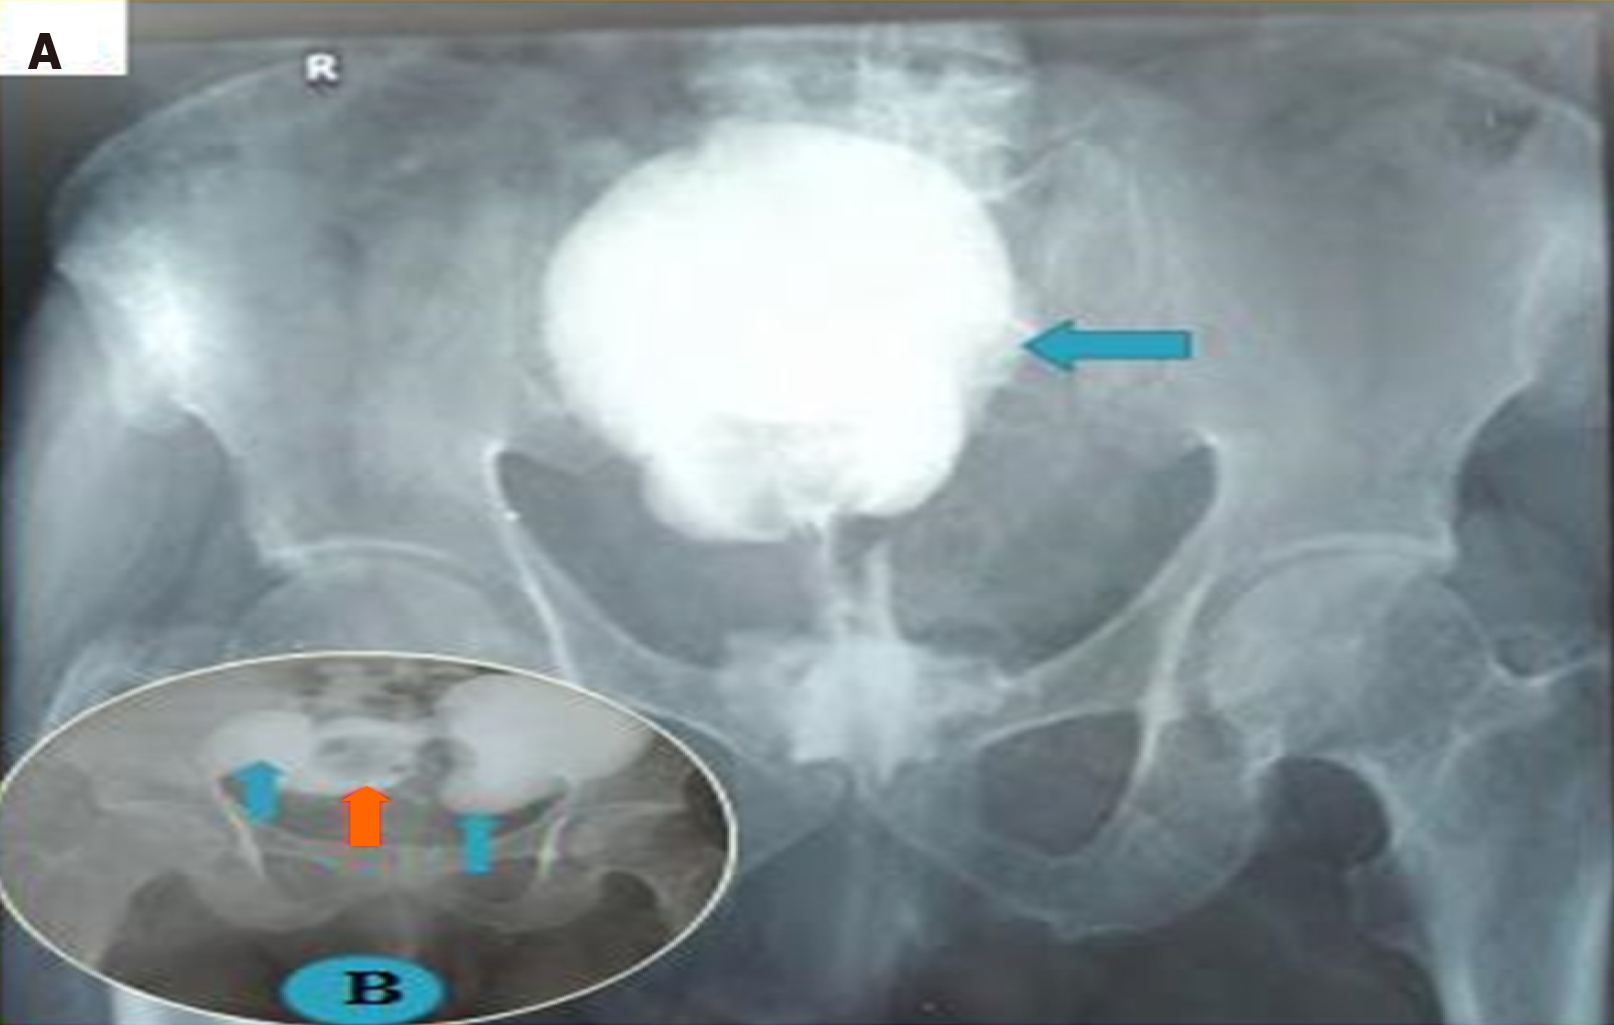

Figure 5 The voiding cystourethrogram findings of the paraureteral diverticulum seen in Figure 2 show right grade five vesicoureteric reflux (green arrow), bladder (blue arrow), paraureteral diverticulum neck (white arrow), paraureteral diverticulum (orange arrow), and faintly demonstrated posterior urethra (yellow arrow) due to diverticular compression during voiding.

A: Cystogram; B: Voiding cystourethrogram.